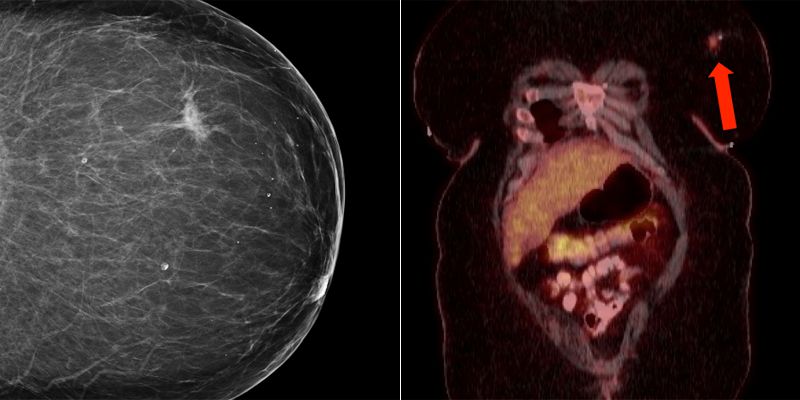

A 41-year-old woman with a past medical history notable for HIV (diagnosed 3 years prior, currently being treated with emtricitabine/rilpivirine/tenofovir) underwent her first screening mammogram, which demonstrated a 1.5-cm irregular focal asymmetry in the left breast. There were no other significant masses, calcifications, or other notable findings in either breast.

A staging PET/CT was obtained, which was unremarkable except for the known lesion in the left breast.